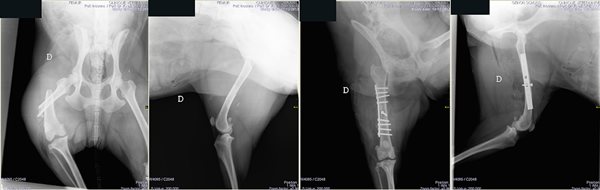

Fixateurs externes. Historiquement, les fixateurs externes sont une des premières techniques de traitement chirurgical des fractures à avoir été utilisés (Lambotte 1902). C'est une technique, aux champs d'application quasi-universels, est actuellement, en chirurgie vétérinaire, principalement réservée aux de traitements des fractures ouvertes, des infections osseuses et de toutes les indications pour lesquelles les méthodes de fixation interne ne sont pas utilisables : le suivi post opératoire laborieux fait qu'on limite cette technique aux indications pour lesquelles elles demeurent incontournables. La possibilité de mise en place à foyer fermé est un de leur principal atout, l'utilisation d'un amplificateur de brillance est dans ce domaine incontournable. La clinique est équipée d'un amplificateur de brillance numérique de dernière génération qui permet le recours à cette technique dans les conditions optimales pour le patient.

- Fracture ouverte grave avec dislocation tarsienne chez un chien

- Traitement par Fixateur externe type Ménard